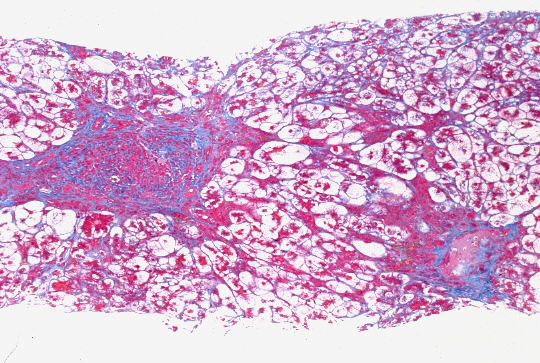

標本;HE,Azan,HBsAgオルセイン&鍍銀の4染色

- 小葉構造;P-P bridging hepatic necrosisをみるも保持されている

- 門脈域;中等度までの線維性拡大、中等度までの単核球主体の炎症性細胞浸潤、小葉間胆管の障害像、細胆管増生、胆汁栓

- 実質域;架橋形成性壊死 (bridging hepatic necrosis)、肝細胞の風船様膨化と再生性肝細胞、小ないし中滴性脂肪沈着を部分的にみる、羽毛状変性と風船様膨化、合胞性多核巨細胞の出現、ロゼット形成(偽腺管構造)、胞体内凝集傾向、核内空胞

肝細胞にビリルビン色素、Ground-glass所見は認めない

HBsAgオルセイン;陰性(Marcophage or Kupffer's cellsに陽性;Ce-L)

病理組織診断;急性肝炎、架橋形成性壊死を伴う(重症型)

Acute hepatitis with bridging necrosis